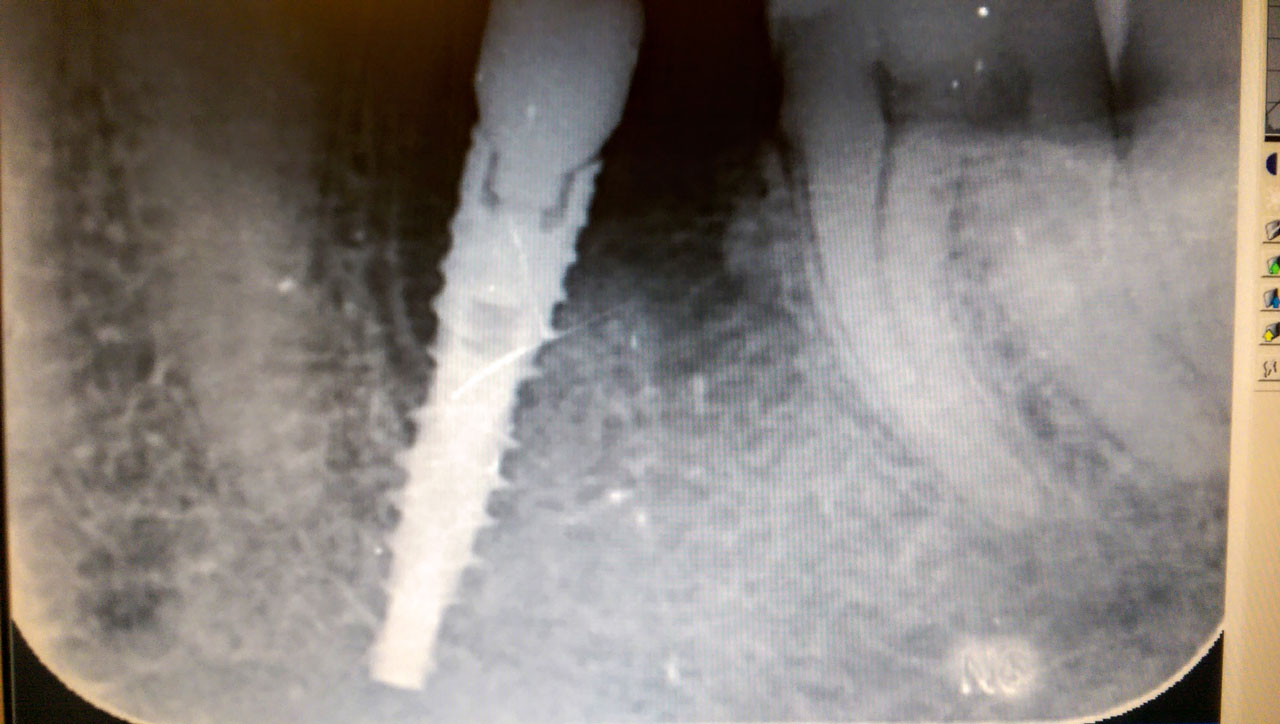

Az azonnal terhelhető implantátum a hagyományos verziókkal szemben, sokkal gyorsabb megoldást kínál és emellett sok más előnyös tulajdonsággal rendelkezik. Az enyhébb fájdalommal járó kezelés már rögtön foghúzás után alkalmazható, így kifejezetten kisebb számú beavatkozást igényel. A gyógyulási folyamat is rövidebb, hiszen a beavatkozások száma körülbelül 3-8 közé tehető, szemben a hagyományos eljárással, aminek során 8-25 alkalommal is meg kell látogatni az orvost. Az azonnal terhelhető implantátum anyagilag is kedvezőbb, sőt, az említett klinika remek kedvezményt is hirdet, aminek keretében 40%-kal kevesebbet kell fizetnie mindazoknak, akik nyolcnál több implantátumot rendelnek.

Az azonnal terhelhető implantátum pusztán 3 nap alatt behelyezhető és utána Ön gyönyörű fogsorral térhet haza.